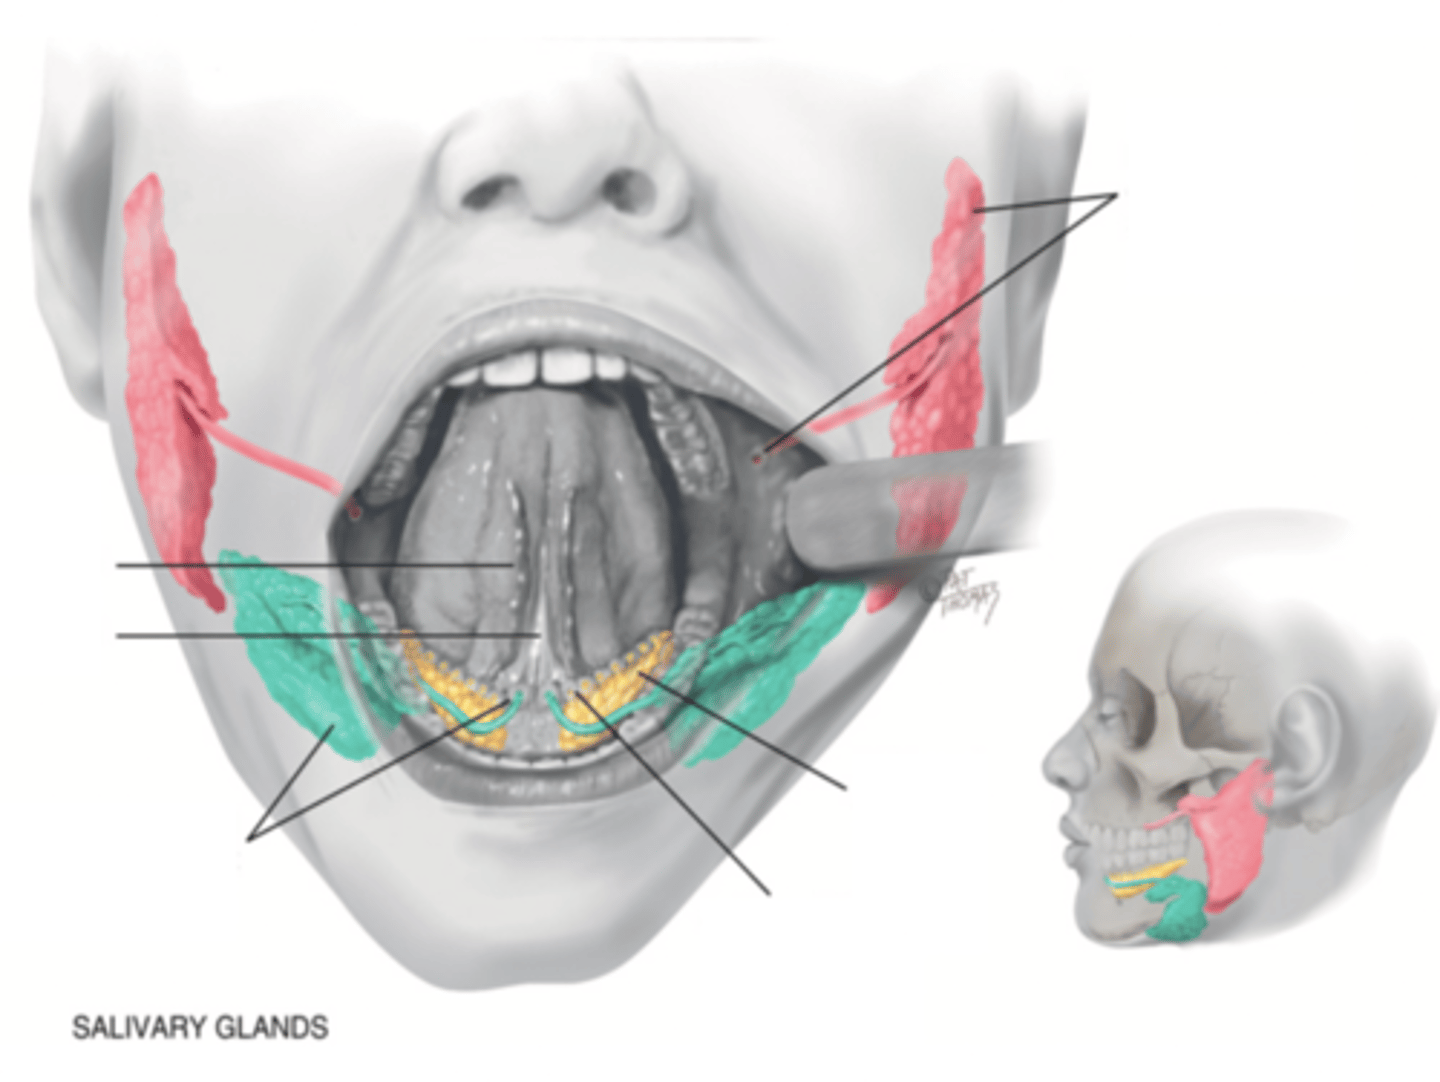

Salivary Glands

- Parotid

- Submandibular

- Sublingual

Parotid Gland

Salivary gland within the cheek, just anterior to the ear (red)

Submadibular Gland

Salivary gland under the mandible (green)

Sublingual Gland

Salivary gland under the tongue (yellow)